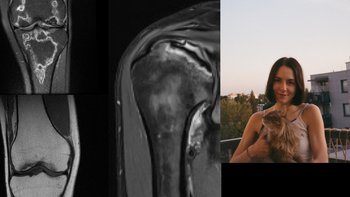

Platforma obsługuje zbiórki w kategoriach takich jak: leczenie i rehabilitacja, operacje w Polsce i za granicą, pomoc po wypadku, choroba przewlekła, odbudowa po pożarze lub powodzi, wsparcie finansowe dla osób w kryzysie, pomoc humanitarna, opieka nad zwierzętami oraz wiele innych nagłych potrzeb.